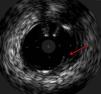

The procedure was performed by radial approach using a 7F guiding catheter. Plaque preparation was performed with rotational atherectomy using a 1.5 mm burr (Figure 3) and further predilation with a cutting balloon (3-3.5 mm). After balloon dilatation, rupture of severely calcified plaque was detected by IVUS (Eagle Eye; Volcano Corporation, Rancho Cordova, CA, USA), so we proceeded to implant a 3.5 mm×20 mm CRE 8 DES in the LM and LAD (Figures 4 and 5). At this point the wire was accidentally pulled back and was reintroduced into the LM and LAD. Post-dilatation was performed with a 4 mm non-compliant balloon. IVUS examination with manual pull-back at this stage revealed that the proximal part of the stent in the LM had been crushed as a result of lateral reintroduction of the wire through a proximal stent strut. The patient remained stable with normal flow in the LM and LAD. Guided by IVUS, a second wire (Sion, Asahi Intecc, Japan), with a 30° bend in its 1 mm distal tip, was introduced within the crushed stent segment (Figure 6). Once the guidewire was positioned inside the stent, progressive dilations with small (1.5 mm) to large (4 mm) balloons were performed until the stent regained its cylindrical shape (Figure 7). IVUS exploration detected an image suggesting dissection in the proximal end of the stent (Figure 8), and so a second DES (4 mm×8 mm Onyx) was implanted in the ostial-proximal segment of the LM, overlapping the previous stent (Figure 9), with an adequate angiographic final result (Figures 10 and 11). IVUS revealed correct stent expansion and apposition in the LM (Figure 12).